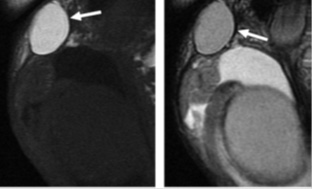

Атерома мрт

Атерома мрт 113 фото